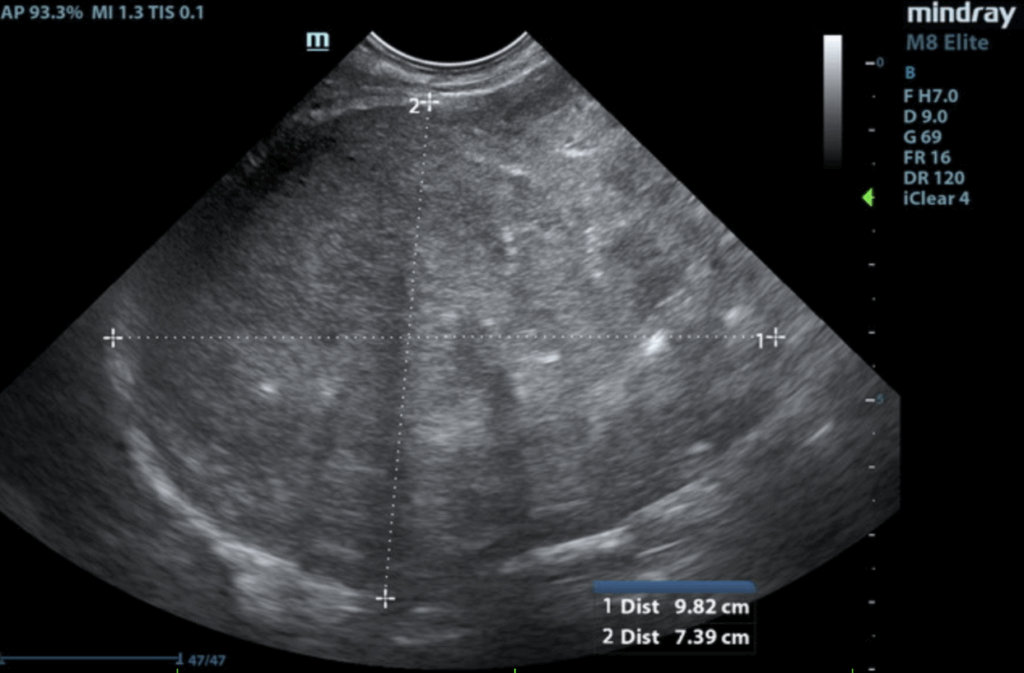

Spleen:

The spleen revealed an expansive parenchymal mass that measured 10+ cm without evidence of cavitation. Hyperechoic fat was noted around the spleen. This is consistent with inflammation.